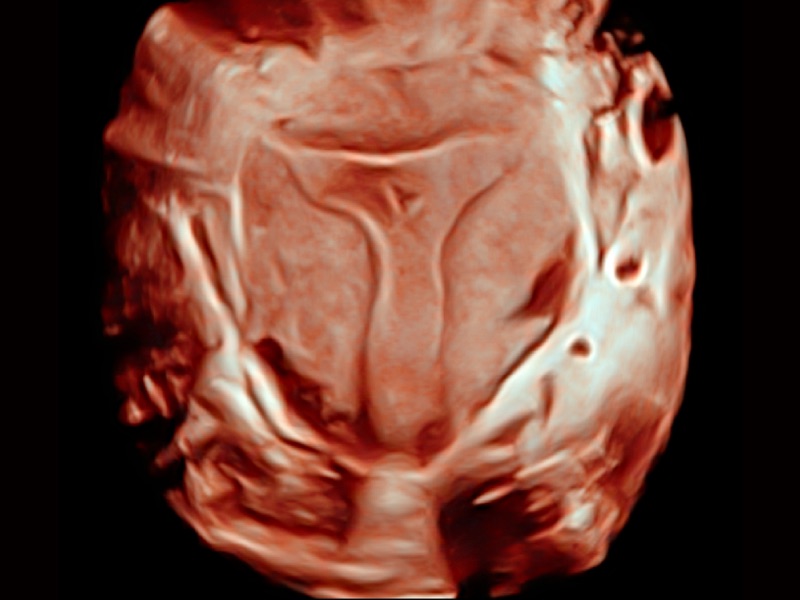

• 光影成像

三维光影成像技术采用新型的渲染方式,增强边缘信息,使得轮显示清晰完整,为临床提供丰富、直观的三维结构,提供临床诊断准确性。

临床图